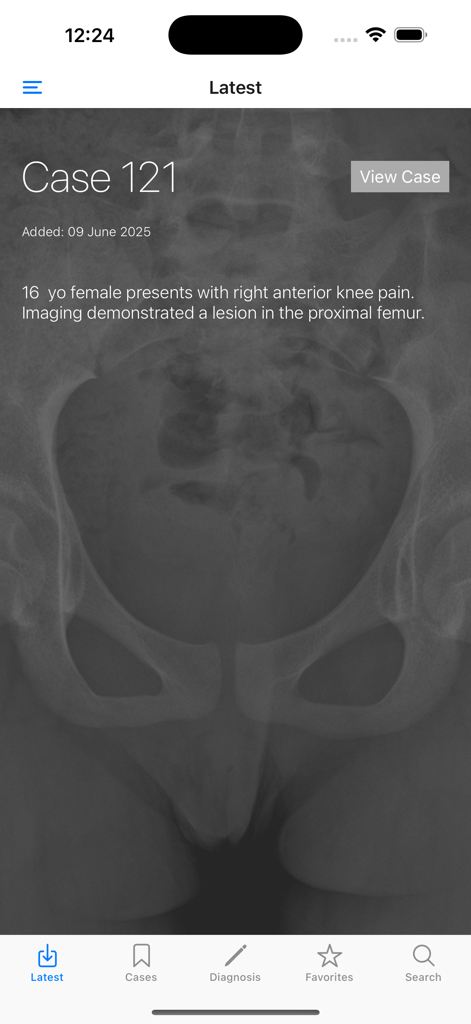

BoSTT - BoSTT app clinical case interface showing a bone tumour patient history with a background pelvic x-ray image.

BoSTT app clinical case interface showing a bone tumour patient history with a background pelvic x-ray image.